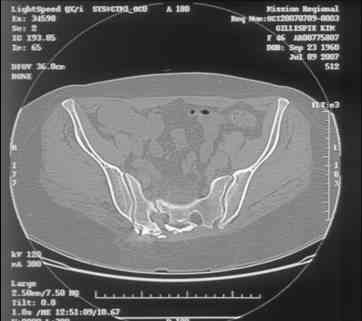

Here is a magnified view. Sorry about the quality but the CT was scanned into our system.

Thank you...it might help to remove the disengaged and other iliosacral screws then insert longer lag screws into the upper sacral segment and if anatomically feasible into the second sacral segment as well.

You could do it percutaneously and even add an electrical stimulation device if that seems reasonable.

At this point, I'd ignore the right pubic root issue if asymptomatic.

If simple measures such as those above fail, then you could remove it all, take down the sacral fracture site, refix with alternate techniques, and bone graft.